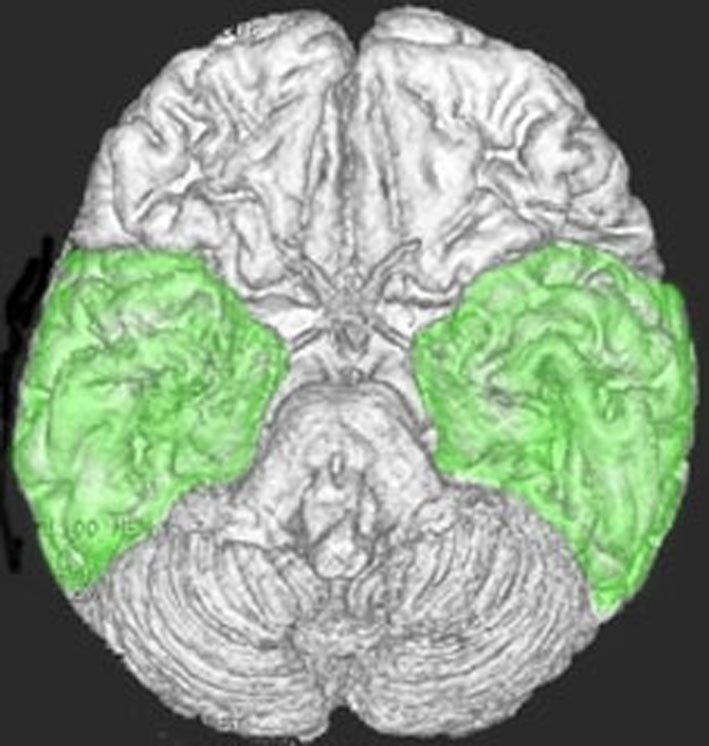

側頭葉の解剖図

側頭葉の解剖図です。表面からは見えませんが,深部の海馬というところには記憶の中枢があります。左側頭葉には言語の中枢もあります。聴覚や味覚,情動などの中枢も側頭葉にあります。

脳の底面(左)と正面(右)から